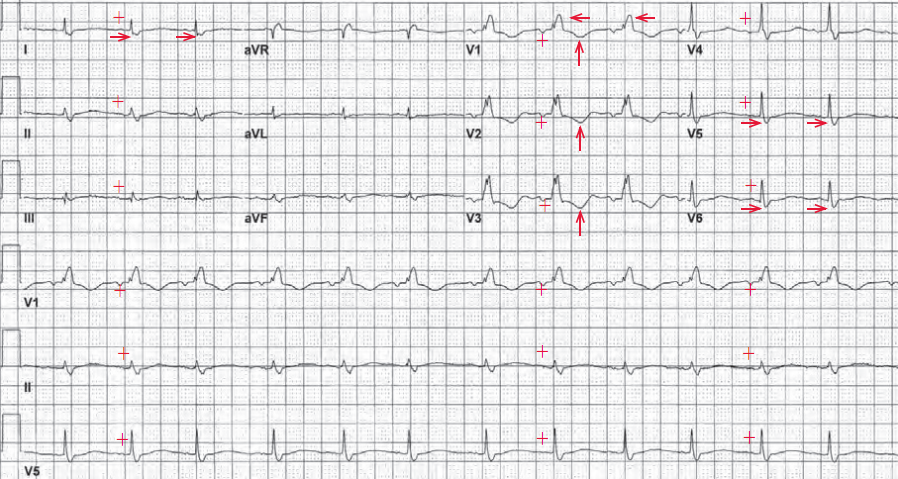

窦性心律:胸导联低电压是什么意思 问题分析:您好,窦性心律是正常的心律,至于胸导联低电压,可能是由于

病情描述(发病时间、主要症状、症状变化等):我心电图查出窦性心律、胸导联低电压左·丅波异常,最近常有

问题描述:(女,24)你好 我想问一下 窦性心律 胸导联低电压 是什么意思啊 医生回答(1) 杨丹 医师 西昌市中

检查心电图 说窦性心律不齐 胸导联低电压 部分导联T波异常

今天去医院检查,医生建议我做了心电,结果是窦性心律 电轴左偏 左胸导联低电压。但是医生没